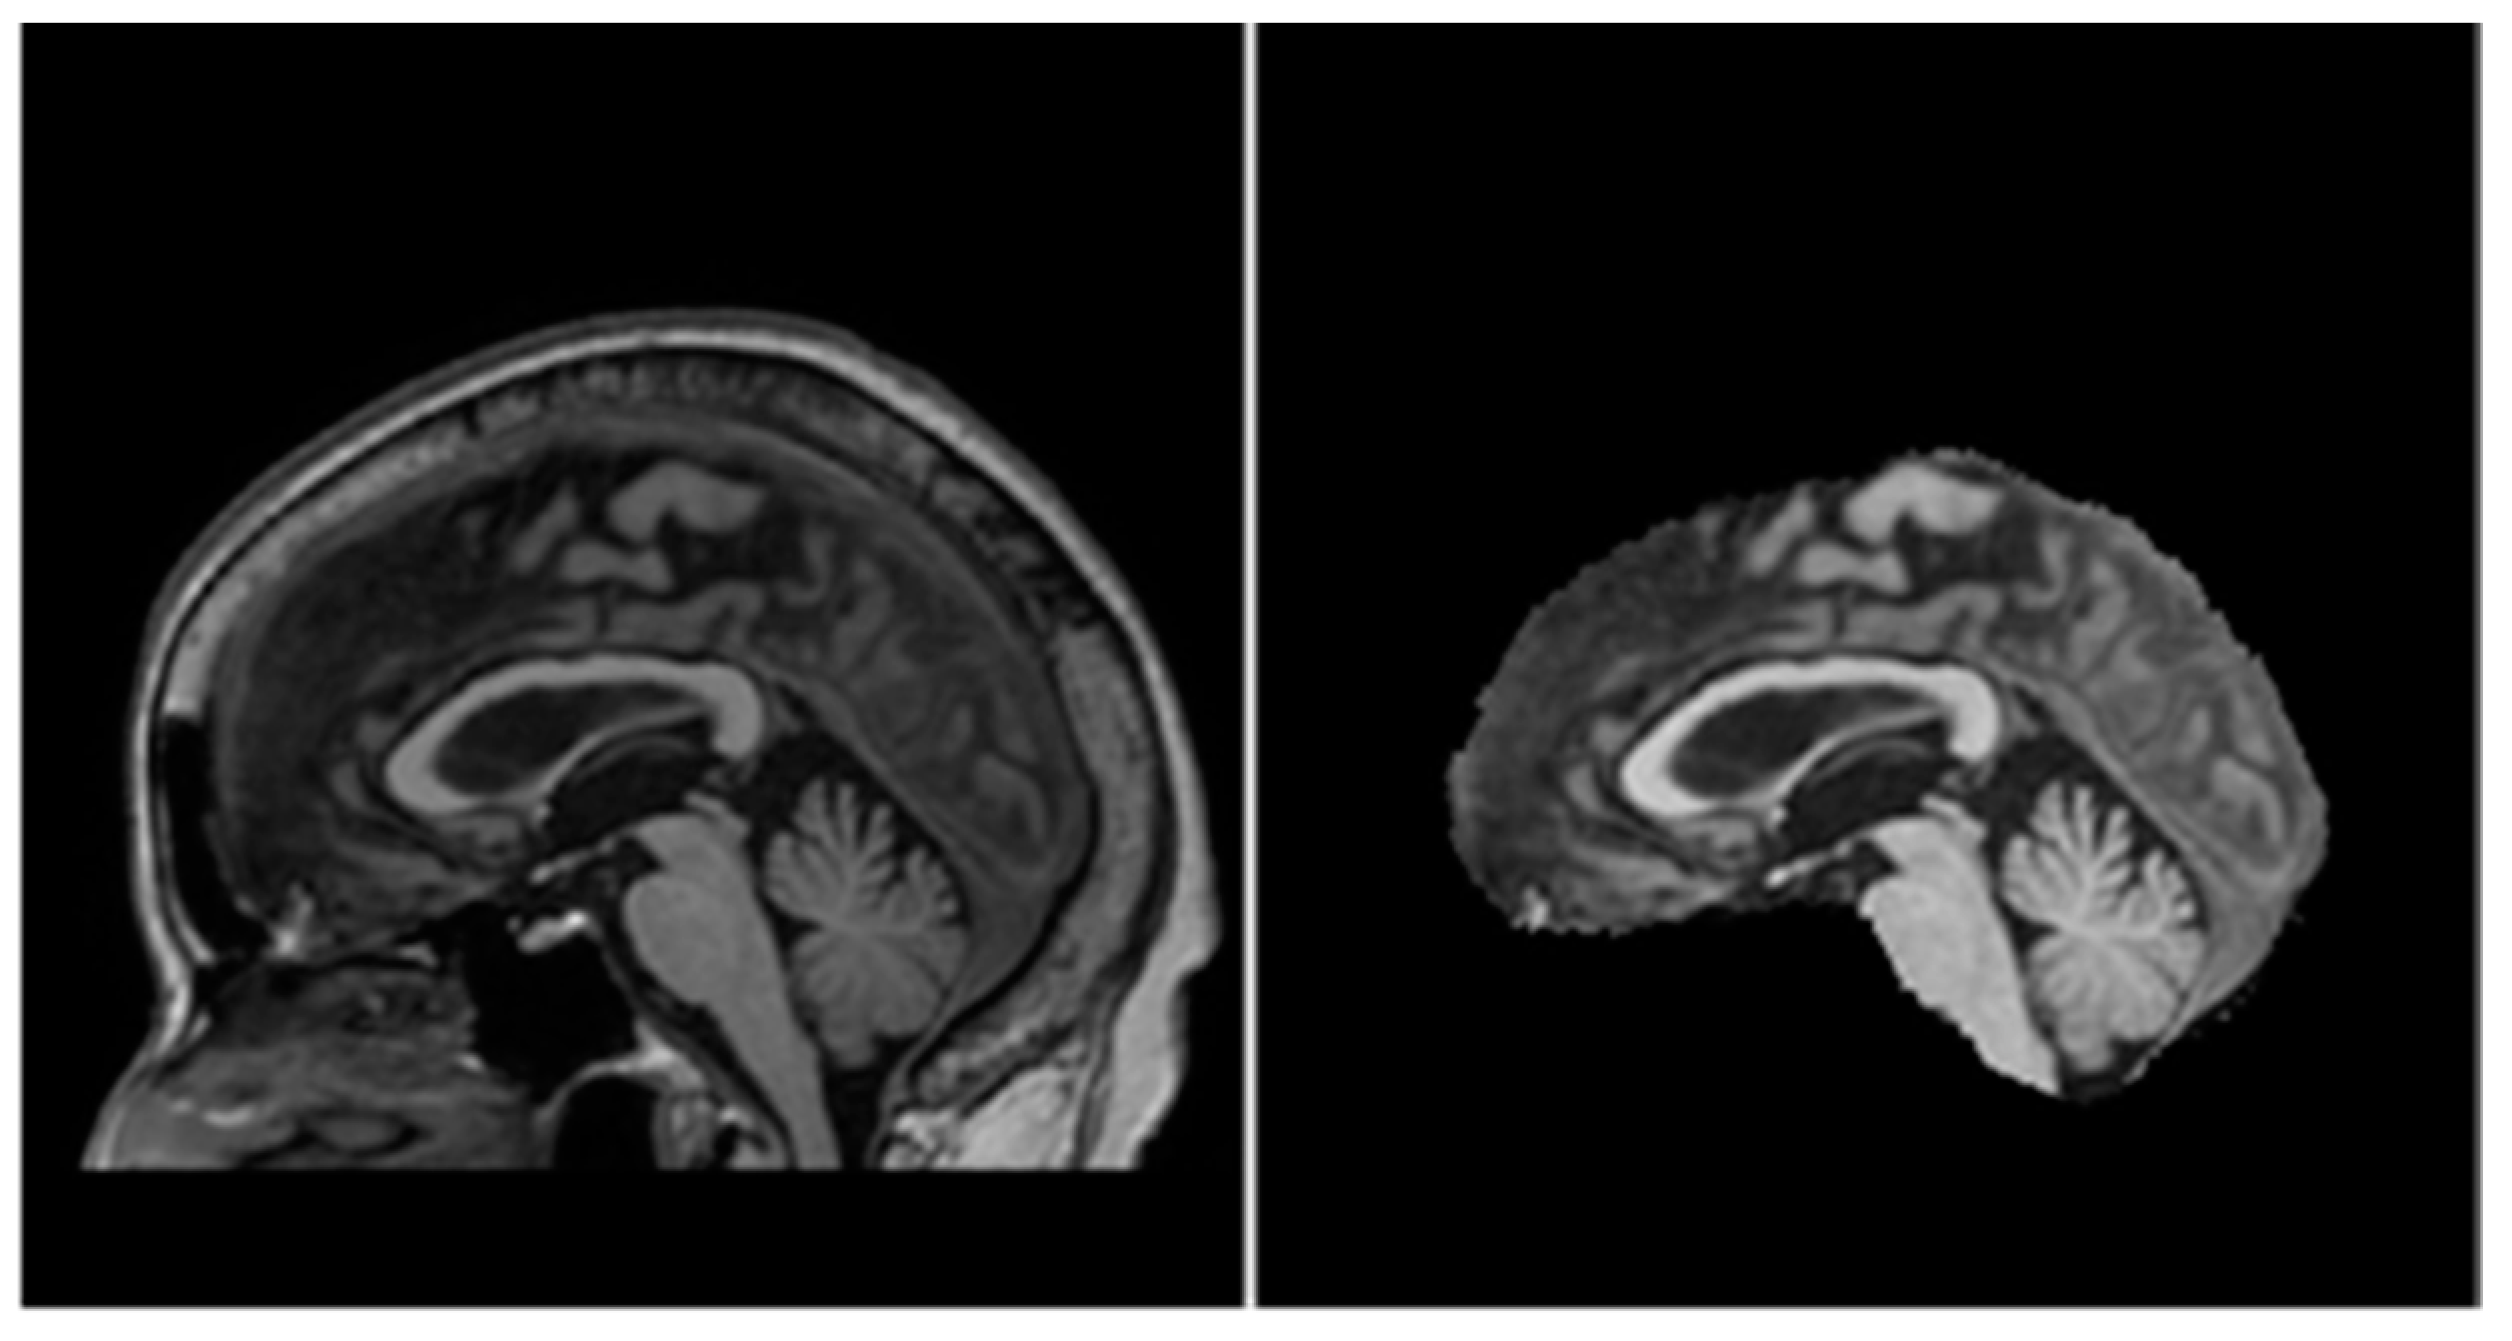

In 2013, a joint project between the European Alzheimer’s Disease Consortium (EADC) and Alzheimer’s Disease Neuroimaging Initiative (ADNI) came up with a standardized protocol for manual segmentation of the hippocampus from MRI scans known as the EADC-ADNI Harmonized Protocol (HarP) [32]. Further follow-up studies showed a significant increase in inter-rater intraclass correlation coefficient (ICC) when experts performing manual segmentations switched to using HarP [8,33]. HarP was also pathologically validated by comparison of HarP segmentations and post-mortem MRI scans of AD patients [34]. Upon establishing the validity of the HarP segmentation method, the EADC-ADNI team also recognized that many automated segmentation algorithms required a large sample of brain MRI volumes and their corresponding hippocampus segmentation masks (segmented with HarP) for training. Therefore, a dataset consisting of 135 brain MRI volumes complete with the benchmark HarP-segmented hippocampus masks was created for use in further research [35]. More information regarding the EADC-ADNI HarP data (including steps to download them) can be found in [36]. It should be noted that for every brain MRI volume, there were two hippocampus segmentation masks corresponding to the left and right hippocampus. A sample coronal view of a brain MRI volume and its corresponding combined hippocampus masks can be seen in Figure 4.

Figure 4.

Sample coronal view from brain MRI (left) and combined hippocampus masks (right) of subject 002_S_0559.

Each brain MRI volume was a cuboid with dimensions of 197 × 233 × 189; each voxel contained a real number representing the intensity of that voxel in the MRI scan. Note that unlike colored images with three RGB channels, each volume only had one channel because MRI scans produce grayscale images.